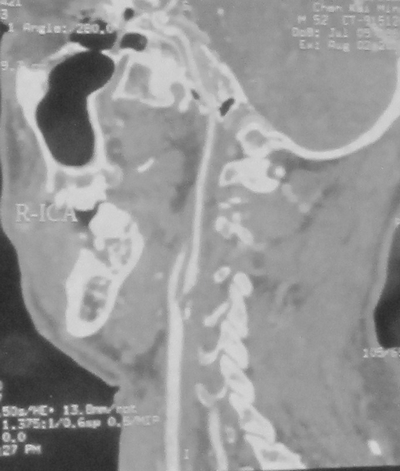

CT检查示:右侧颞叶及基底节区脑梗塞(2012年7月14日)。颈动脉B超示:右颈动脉球部及颈内动脉起始段狭窄70-99%;颈动脉CTA示右侧颈总动脉分叉处重度狭窄(90%)。